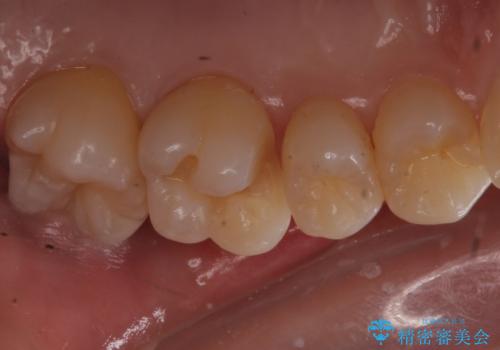

歯と歯の間の虫歯 ゴールドインレーでの修復

見た目よりも精度を優先したいとのことだったため、ゴールドインレーでの修復処置を行いました。

- 左上6 ゴールドインレー 77,000円費用は治療当時の料金となります

ゴールドの修復物は高い精度を出すことができるため非常に適合の良いものを装着することができます。